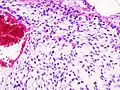

| Histopathologic image of chondrosarcoma of the chest wall. Surgical resection of recurrent mass. H & E stain. | |